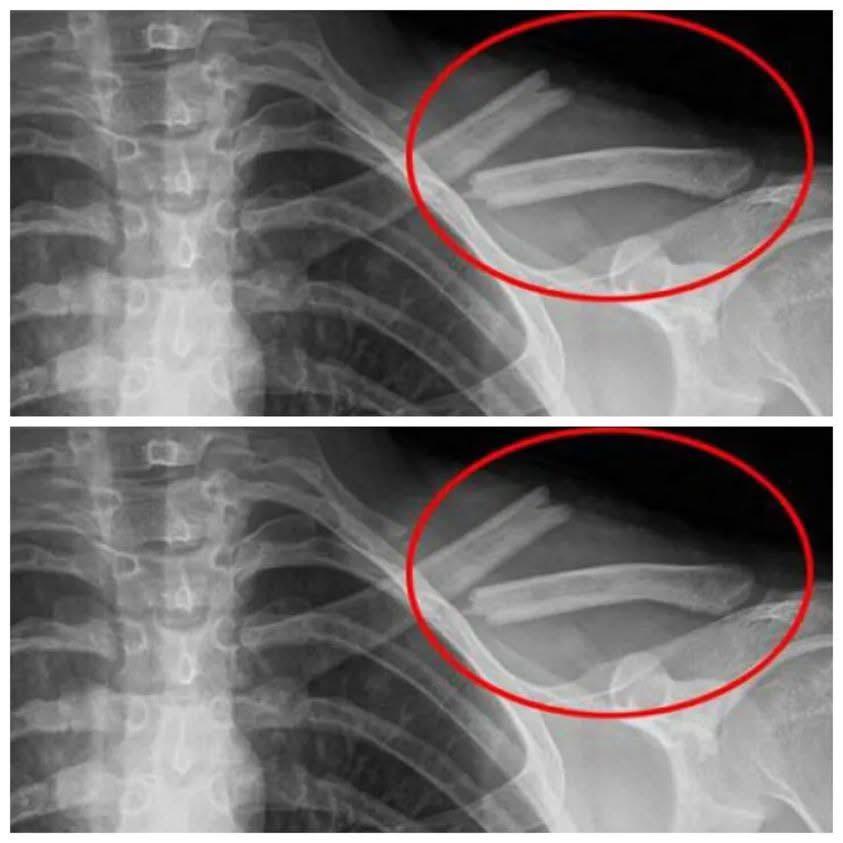

Bone Weakening: High soda intake depletes calcium, increasing osteoporosis risk.